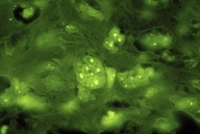

03400119

OLYMPUS CORPORATION

ヒト皮膚扁平上皮癌